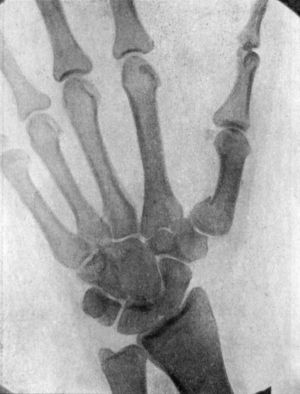

49.Radiogram showing Fracture of Navicular (Scaphoid) Bone111

50.Dorsal Dislocation of Wrist at Radio-carpal Articulation113

51.Radiogram showing Forward Dislocation of Navicular Bone114